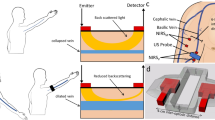

We derived the forearm microvascular bed volumes from the sum of oxygenated hemoglobin/myoglobin (oxyHb/Mb) and deoxygenated Hb/Mb (deoxy Hb/Mb) μM concentrations ([Hb]tot/[Mb]tot) measured using a NIMO-4 continuous-wave photometer (Nirox srl, Brescia, Italy)8. Then, we calculated the blood volume per 100 mL of tissue after accounting for the mean corpuscular hemoglobin concentration, mean corpuscular volume, and hematocrit levels in each participant. Since the Hb in arterioles accounts for only 3% of the NIRS signal, and because these vessels as well as capillaries are poorly distensible9, the changes in [Hb]tot during venous compression represented almost exclusively the changes that occurred in the venules and small veins. Data were acquired at a sampling time of 0.1 s, thus facilitating analysis of rapid changes in the [Hb] levels with a dedicated NIMO software program.

We performed measurements in the dominant forearm and positioned a NIRS probe at the top of the flexor digitorum superficialis (FDS) muscle and verified the correct placement of the probe visually. A pneumatic cuff was placed around the arm 5 cm proximal to the antecubital crease, with its tube connected to an automatic inflation system (model E-20, Hokanson Rapid Cuff Inflator and AG101 Air Source; PMS Instruments Ltd, Maidenhead, UK) capable of reaching a manually predefined pressure in less than 0.5 s. To ensure that there were no differences in hydrostatic pressure due to the position of the forearm during measurement and that no correction factor was needed, we restrained the forearm in a plastic frame at an angle of 135° in relation to the upper arm and placed the NIRS probe at the same level as the right atrium12. The study took place in temperature-controlled rooms, and participants were made to lie down in a comfortable position. To extend the range of values, we experimentally increased the extravascular pressure by graded muscle isometric contractions in healthy participants.

For this method, we developed an analog resistor–capacitance model of the vascular system17, by adapting the model proposed by Van Vo et al.18. As an analogy with the electric scheme, the current, difference in electric potential, resistances, and capacitance represented blood flow, pressure difference, vascular resistance, and vascular compliance, respectively (Fig. 2a).

(a) An electric scheme of the resistor-capacitance model. Pa and Pv are the arterial and venular pressure. Pcuff: cuff pressure, C: venular compliance, Ra: total resistance upstream of venules, R(Pcuff): the variable resistance generated by the cuff pressure. (b) Venular volume as a function of the cuff pressure. The volume is constant for P < P0. For P > P0 it grows according to the equations derived from the model picture in Fig. 2a (see SM for the derivation). C1: compliance associated with recruitment of the microvascular bed, C2: compliance associated with vessel elasticity, V: venular volume (ml), V0: venular volume at baseline (ml). Vu and Vs: unstressed and stressed volume (ml).

We modeled the vascular compartment between the arteries and veins upstream of the pneumatic cuff. The initial and final pressures on our circuit were represented by the arterial pressure Pa and Pcuff. We defined Ra as total resistance in the upstream venules, C as venular compliance, R as venular resistance and Pv as venular pressure. In our model, both R and C depended on the Pcuff because of venular pressure transmission. In particular, R equals the baseline value when the Pcuff is lower than the MSFP value and grows linearly when Pcuff rises above it. In our model, up to a certain Pv value, C reflects the recruitment of the microvascular bed (C1). Above this Pv value, the vascular bed is fully recruited and venular compliance (C2) reflects the vessel wall elasticity.

Based on this premise and by assuming the blood flow upstream and downstream venular compartment in the steady state as a constant, we derived a relationship between the V0 and Pcuff, which is reported in Fig. 2b. All measurements were taken when the blood flow in the venule section had reached the stationary state after each change in the cuff pressure. Accordingly, we solved the circuit equations in the late-time stationary limit, when the transient phase had ended. When the Pcuff is lower than the MSFP (P0) venular volume equals the sum of Vu and Vs, which is the baseline volume (V0), namely, the volume attained when the Pcuff is not applied. Above P0, venular volume increases as a result of the Pcuff values increase, showing two different slopes corresponding to the vascular bed recruitment and vessel wall elasticity. Calculations and relationships between the variables and details on the model are reported in supplementary methods S1.